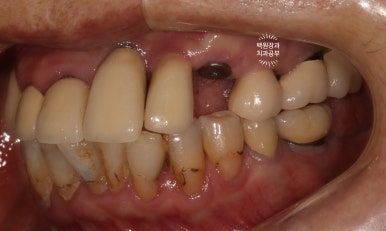

저희 치과에 다니시던 70대 여자 환자분입니다.

잘 보시면, 임플란트가 총 위턱에 9개, 아래턱에 2개 되어있는데 대부분이 아주 유명한 외국 임플란트 제품들입니다. 특히나 위턱 어금니는 스트라우만 standard 제품으로, 제가 가장 신뢰하는 제품 중 하나입니다.

무려 20년이 넘으셨다고 했는데... 임플란트 주위염 하나 없이 너무너무 잘 사용하고 계시더라구요.

처음 오셨을 때 정면 사진입니다.

잘 보시면, 아까 보였던 치과용 파노라마 사진대로 뿌리만 남은 두 개의 치아를 찾아보실 수 있으실거에요. ㅎㅎ

제가 서두에서 어금니에 스트라우만 임플란트가 많다고 말씀드렸는데, (나머지도 branemark 제품으로 보이며, 명품으로 주름잡던 스웨덴 임플란트 입니다.) 이 미친 퍼포먼스의 스위스 임플란트는 20년이 지난 지금도 짱짱한 성능을 자랑하고 있답니다.